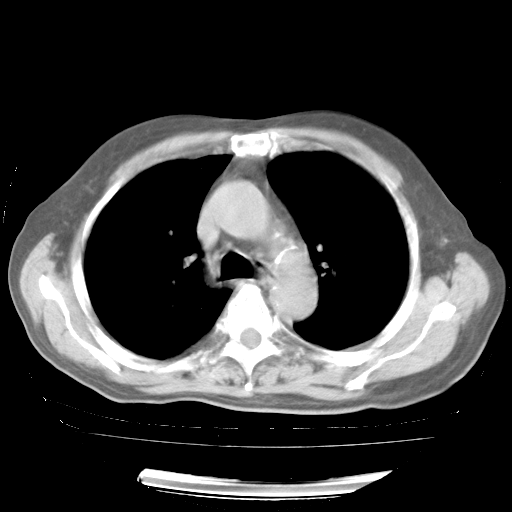

4月28日肺部CT——再次出现类似去年5月9日——透光度降低,“间质性”改变。

4月28日肺部CT——再次出现类似去年5月9日——磨玻璃样、间有“粟粒样”改变。

4月28日肺部CT

个人阅读4.14日肺部CT平扫:纵隔窗无异常,但肺窗示:双下肺内、后基底段有片絮状侵润影,部位以后基底段为著,以间质改变为主,呈急性肺泡炎征像,和首次住院影像学有相似之处。仅是个人读片,明日请相关专家再读片哈。其它建议同上。

1、108#的是4月14日的胸部CT(发此贴时还没看着28日的CT)。14日的胸部CT其实已经出现改变(如108#所述),个人认为28日的胸部CT除纵膈窗疑似有双侧胸膜增厚或少量胸积液(可行胸部B超明确)外,与4月14日对照病变有所加重;2、已经给予“异烟肼、利福平、乙胺丁醇”抗痨治疗?如果是,甲强龙80mg可缓慢减量;如果环磷酰胺已停用,暂不使用;3、中性粒细胞92%,明显升高,目前体温情况?注意合并细菌感染可能,使用左氧氟沙星情况下,是否联用B-内酰胺类抗菌药物?另外是查免疫全套非风湿全套。